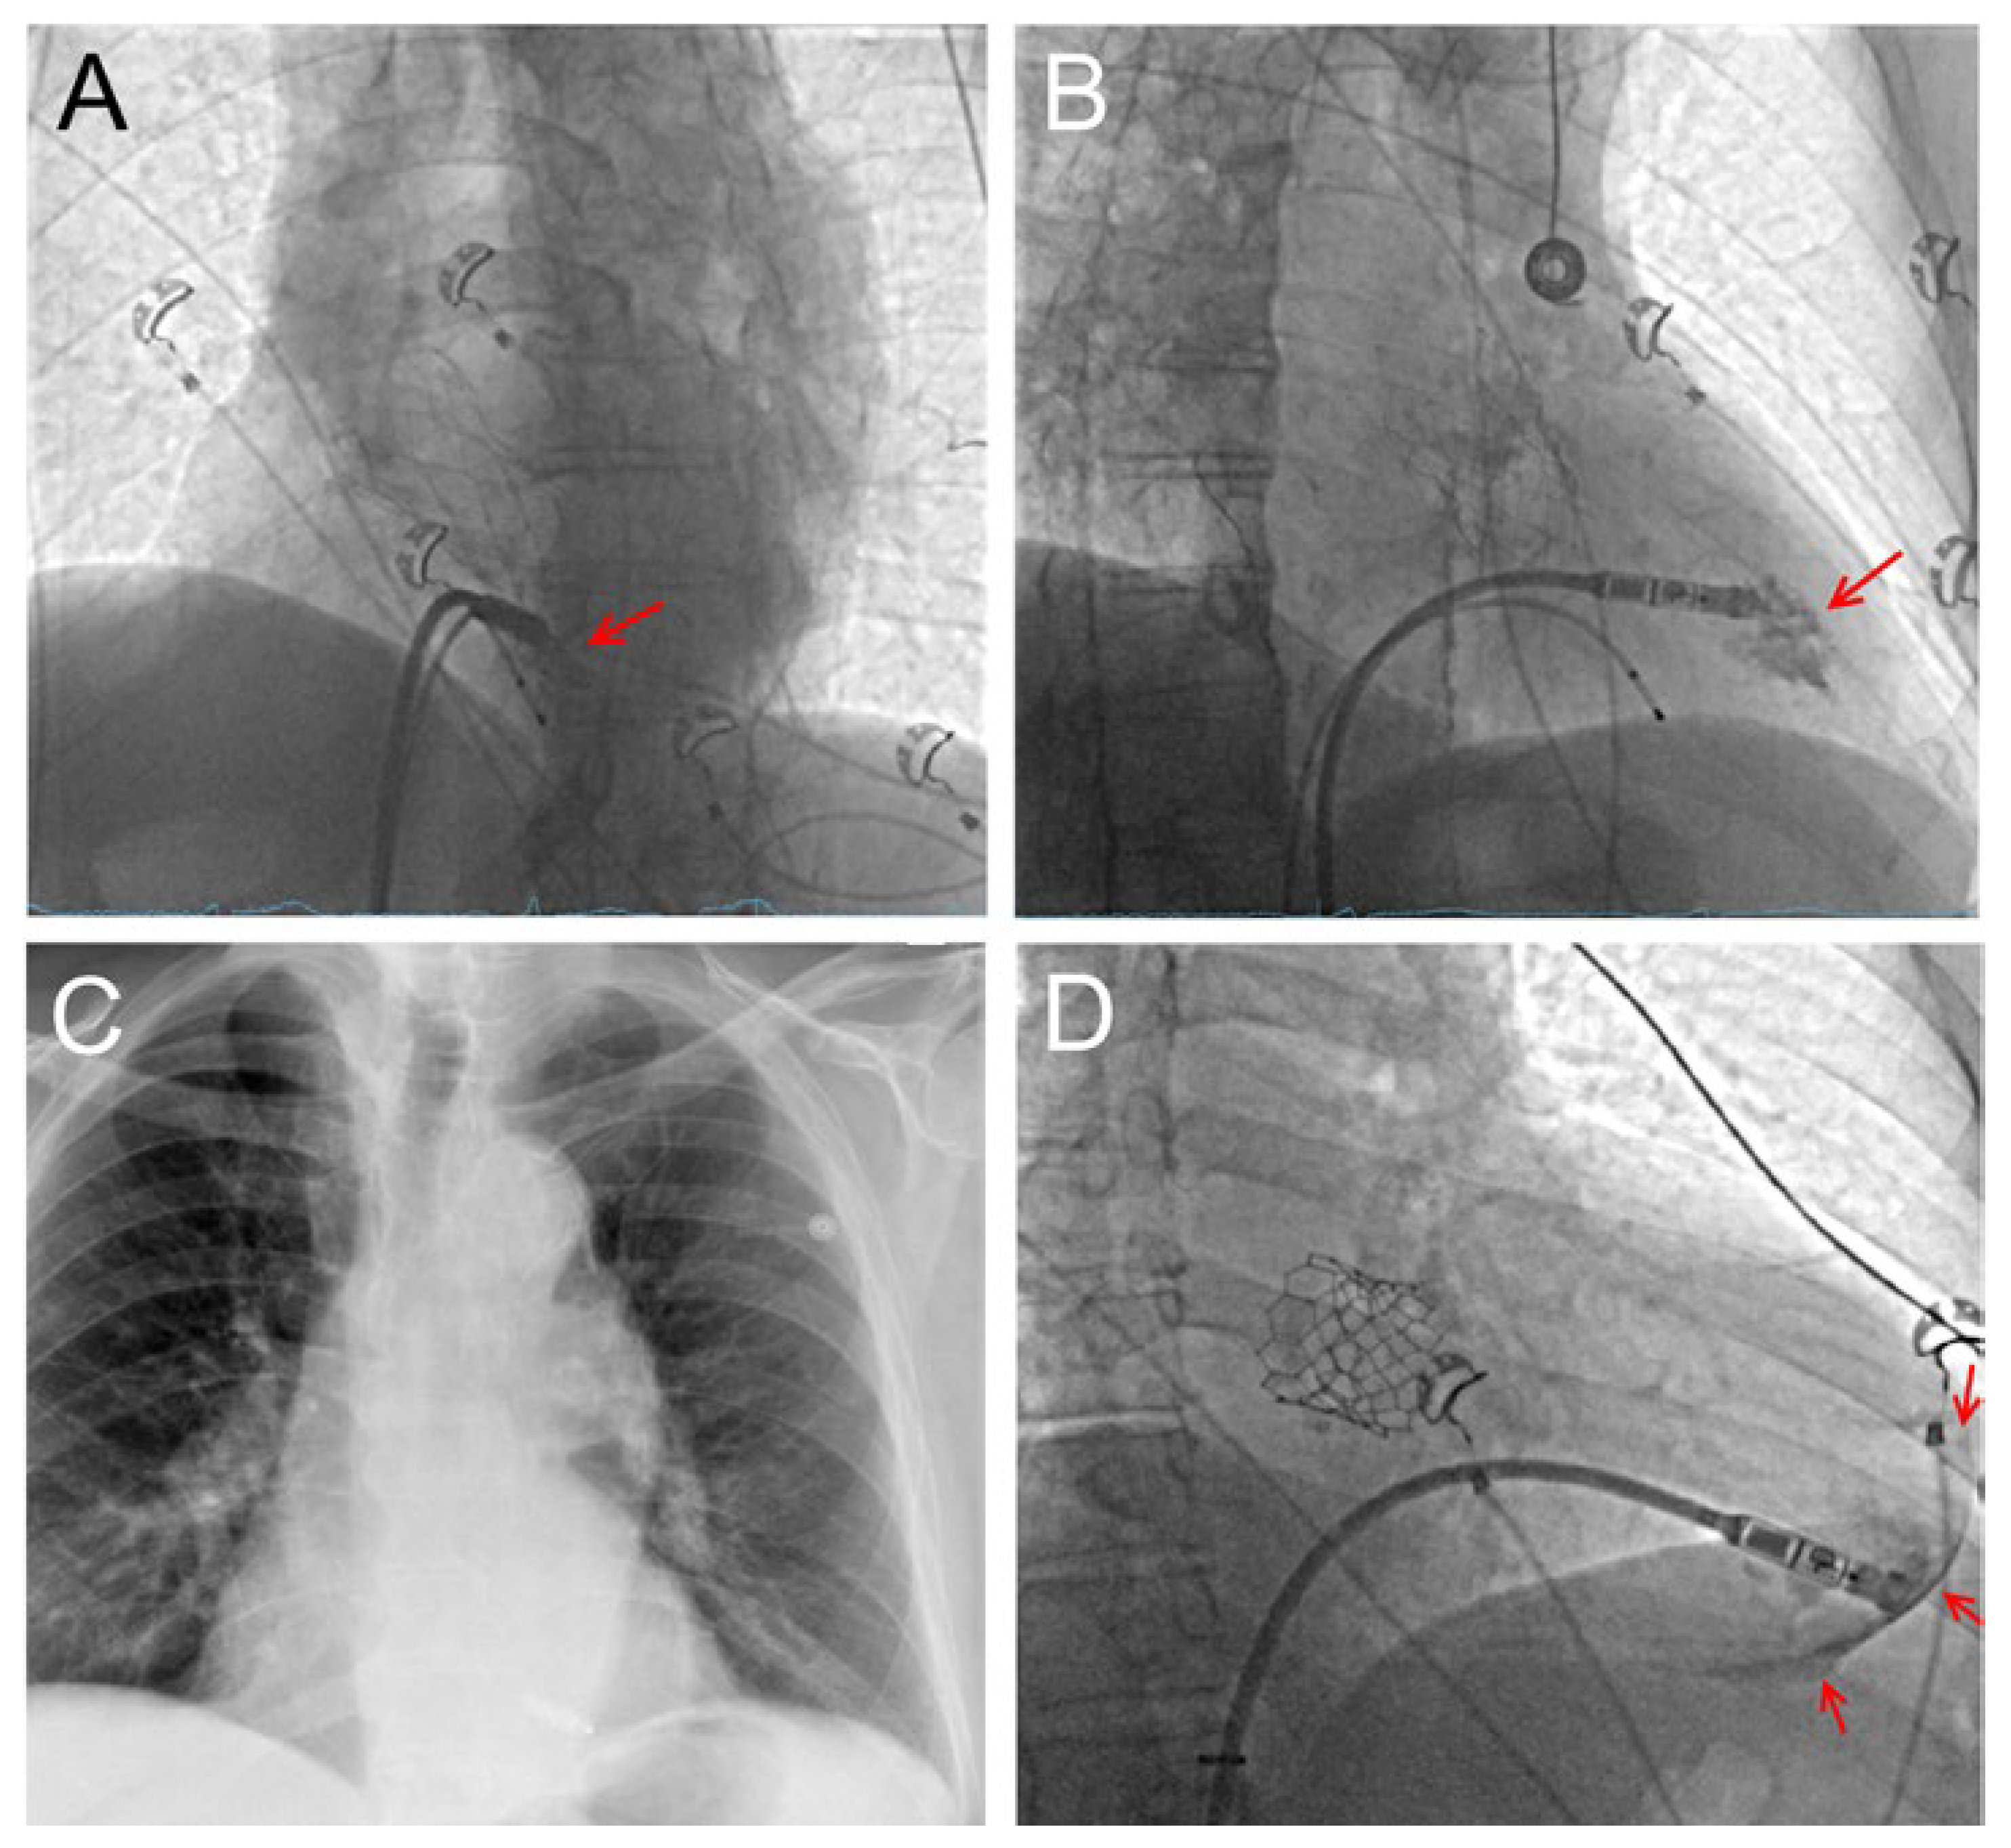

To implant a leadless pacemaker, access is gained via the femoral vein and the system is navigated to the interventricular septum, where it is anchored using a tine-based mechanism or a screw (Figure 1A–C). It can be programmed as a backup pacemaker or in VVIR (ventricular demand rate responsive) mode. During implantation of a leadless PM, caution is warranted, as cardiac perforations caused by the delivery catheter or the device may result in devastating complications requiring immediate cardiac surgery (Figure 1D). However, the overall complication rate of leadless PMs is presumably significantly lower compared to transvenous PMs [4] and appropriate training and sufficient experience results in excellent success rates and outcomes [5]. Naturally, lead-associated complications cannot occur and a subcutaneous pocket is not required, which almost eliminates device infections and the need for device removal. This is important, as percutaneous device extractions after a few years of implantation may be challenging due to encapsulation.

Figure 1. Panels (A,B) Patient with intermittent complete AV block after transcatheter aortic valve implantation (TAVI) undergoing leadless pacemaker implantation. Temporary backup pacing is ensured via an electrophysiology catheter. Panel A shows a LAO view, panel B a RAO view. The red arrow shows the contrast medium, which illustrates that the PM is properly positioned at the interventricular septum. Panel (C) Postoperative X-ray in p.a. projection after device release. Panel (D) Different patient with increasing AV block I° (PQ >400 ms) after TAVI (RAO view). During device positioning, a crescent-shaped contrast medium deposit was seen (arrows), indicative for ventricular perforation. Pericardiocentesis, autotransfusion of circa 1.5 L blood and emergency sternotomy were performed and an RV rupture was sutured. After surgery, the patient recovered well and was dismissed from hospital five days after the complication with a transvenous pacemaker.